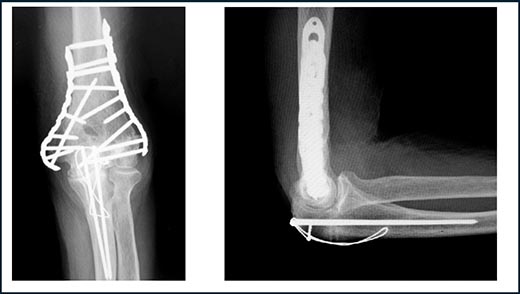

上腕骨顆部関節内骨折や粉砕した骨片がある場合は、肘関節内を直接確認するために尺骨の肘頭(チュウトウ)部で骨切り(骨ノミや電動骨ノコギリを使用)を行います。肘頭に上腕三頭筋(ジョウワンサントウキン)をつけたまま反転し、骨折した部分の手術を行います。この場合は、骨折を固定した後で肘頭を金属ワイヤーで固定します(図6)。

図6.上腕骨顆部関節内骨折:肘頭部を骨切り後、骨折を整復し固定したので、

肘頭はワイヤーで締結してあります。